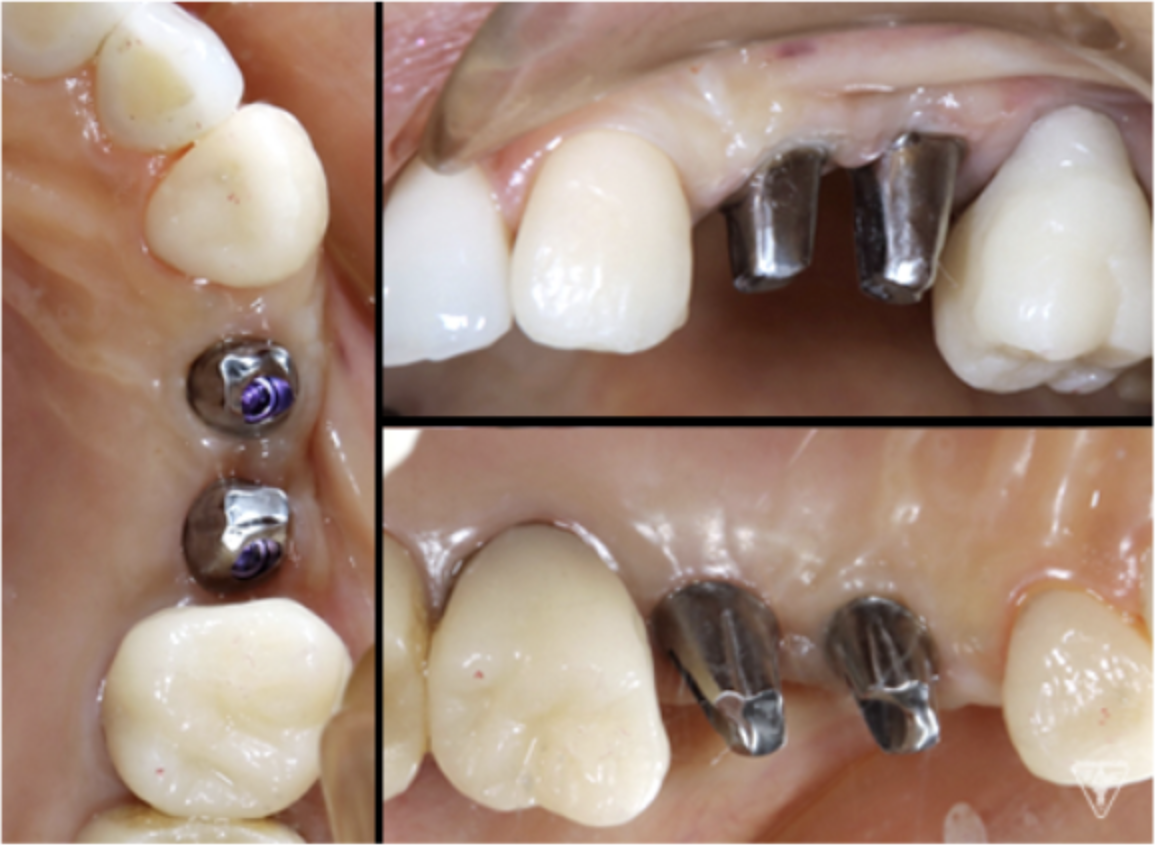

最終補綴物装着時

咬合調整

粉砕効率の高い小さな点による均衝接触をつくります。

咬合様式は、ミューチャリープロテクトオクルージョンを付与しました。